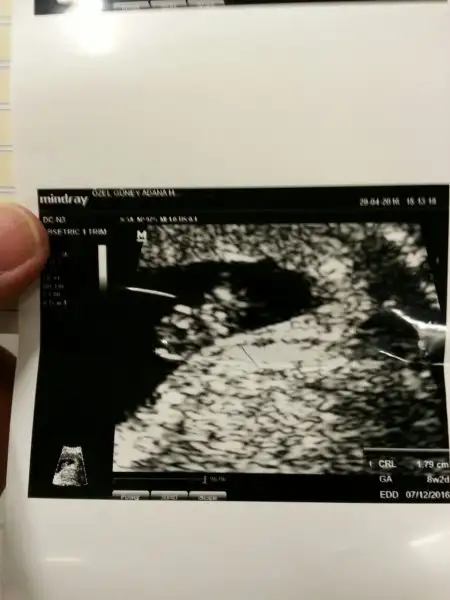

Evet arkadaşlar zeytinimle dr a gittik

8+2 mişiz 1.76mm ne sağ kesede ne sol kesede tam ortadaymış :) yaramaz

Kalp atışlarını dinledik :)

Tahmini doğum tarihi sezeryan olacağı için 1 -2 aralık dedi